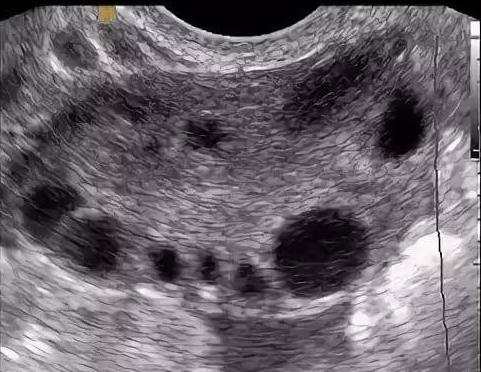

3. Определение объёма яичников + подсчёт антральных фолликулов и оценка их размера при трансвагинальном УЗИ, сделанном на 2–5 день цикла.

При СПКЯ в яичниках много фолликулов – они дают много АМГ. У пациенток с СПКЯ часто выявляется повышенный уровень АМГ – более 3,2 нг/мл. Исключение составляют подростки в течение первых 8 лет после менархе (менархе – первая менструация).